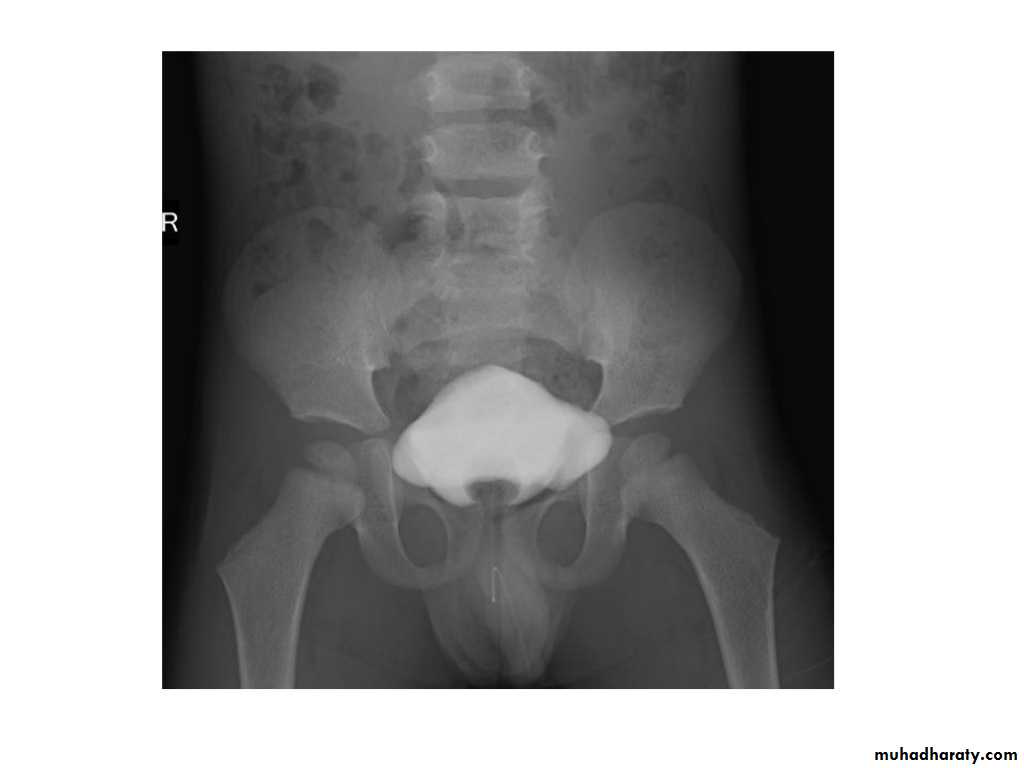

IVU shows

1. The kidneys at low position .2.Close to the spine with long axis parallel to the spine

3. Malrotation manifested by medially directed calyces.

4- The renal pelvis and ureters are anterior and lateral in position.

5- Hydronephrosis and calculi highly associated.